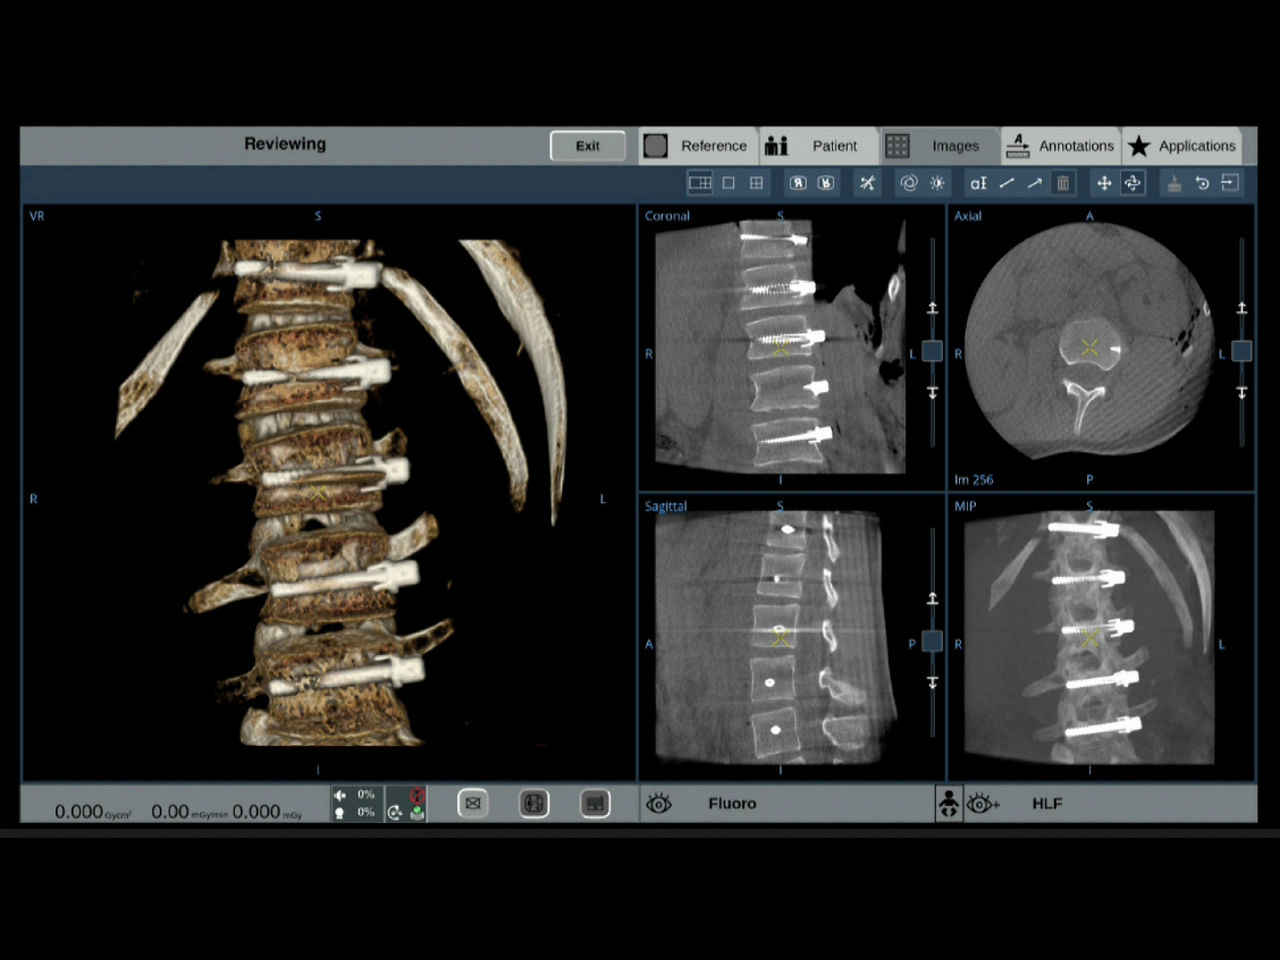

With OEC 3D, comprehensive imaging coverage of 19 cm x 19 cm x 19 cm 3D volumes and exceptional 2D images enables viewing several levels of the spine in the operating room.

The OEC 3D presents five perspectives: Axial, Coronal, Sagittal, MIP, and VR, on a 4K display for clear and detailed review of 3D volumes and 2D images

Review screws with automatic detection and numbering, manually label spine levels, and visualize spinal curvature alignment with Spine Suite, an optional application available with OEC 3D.